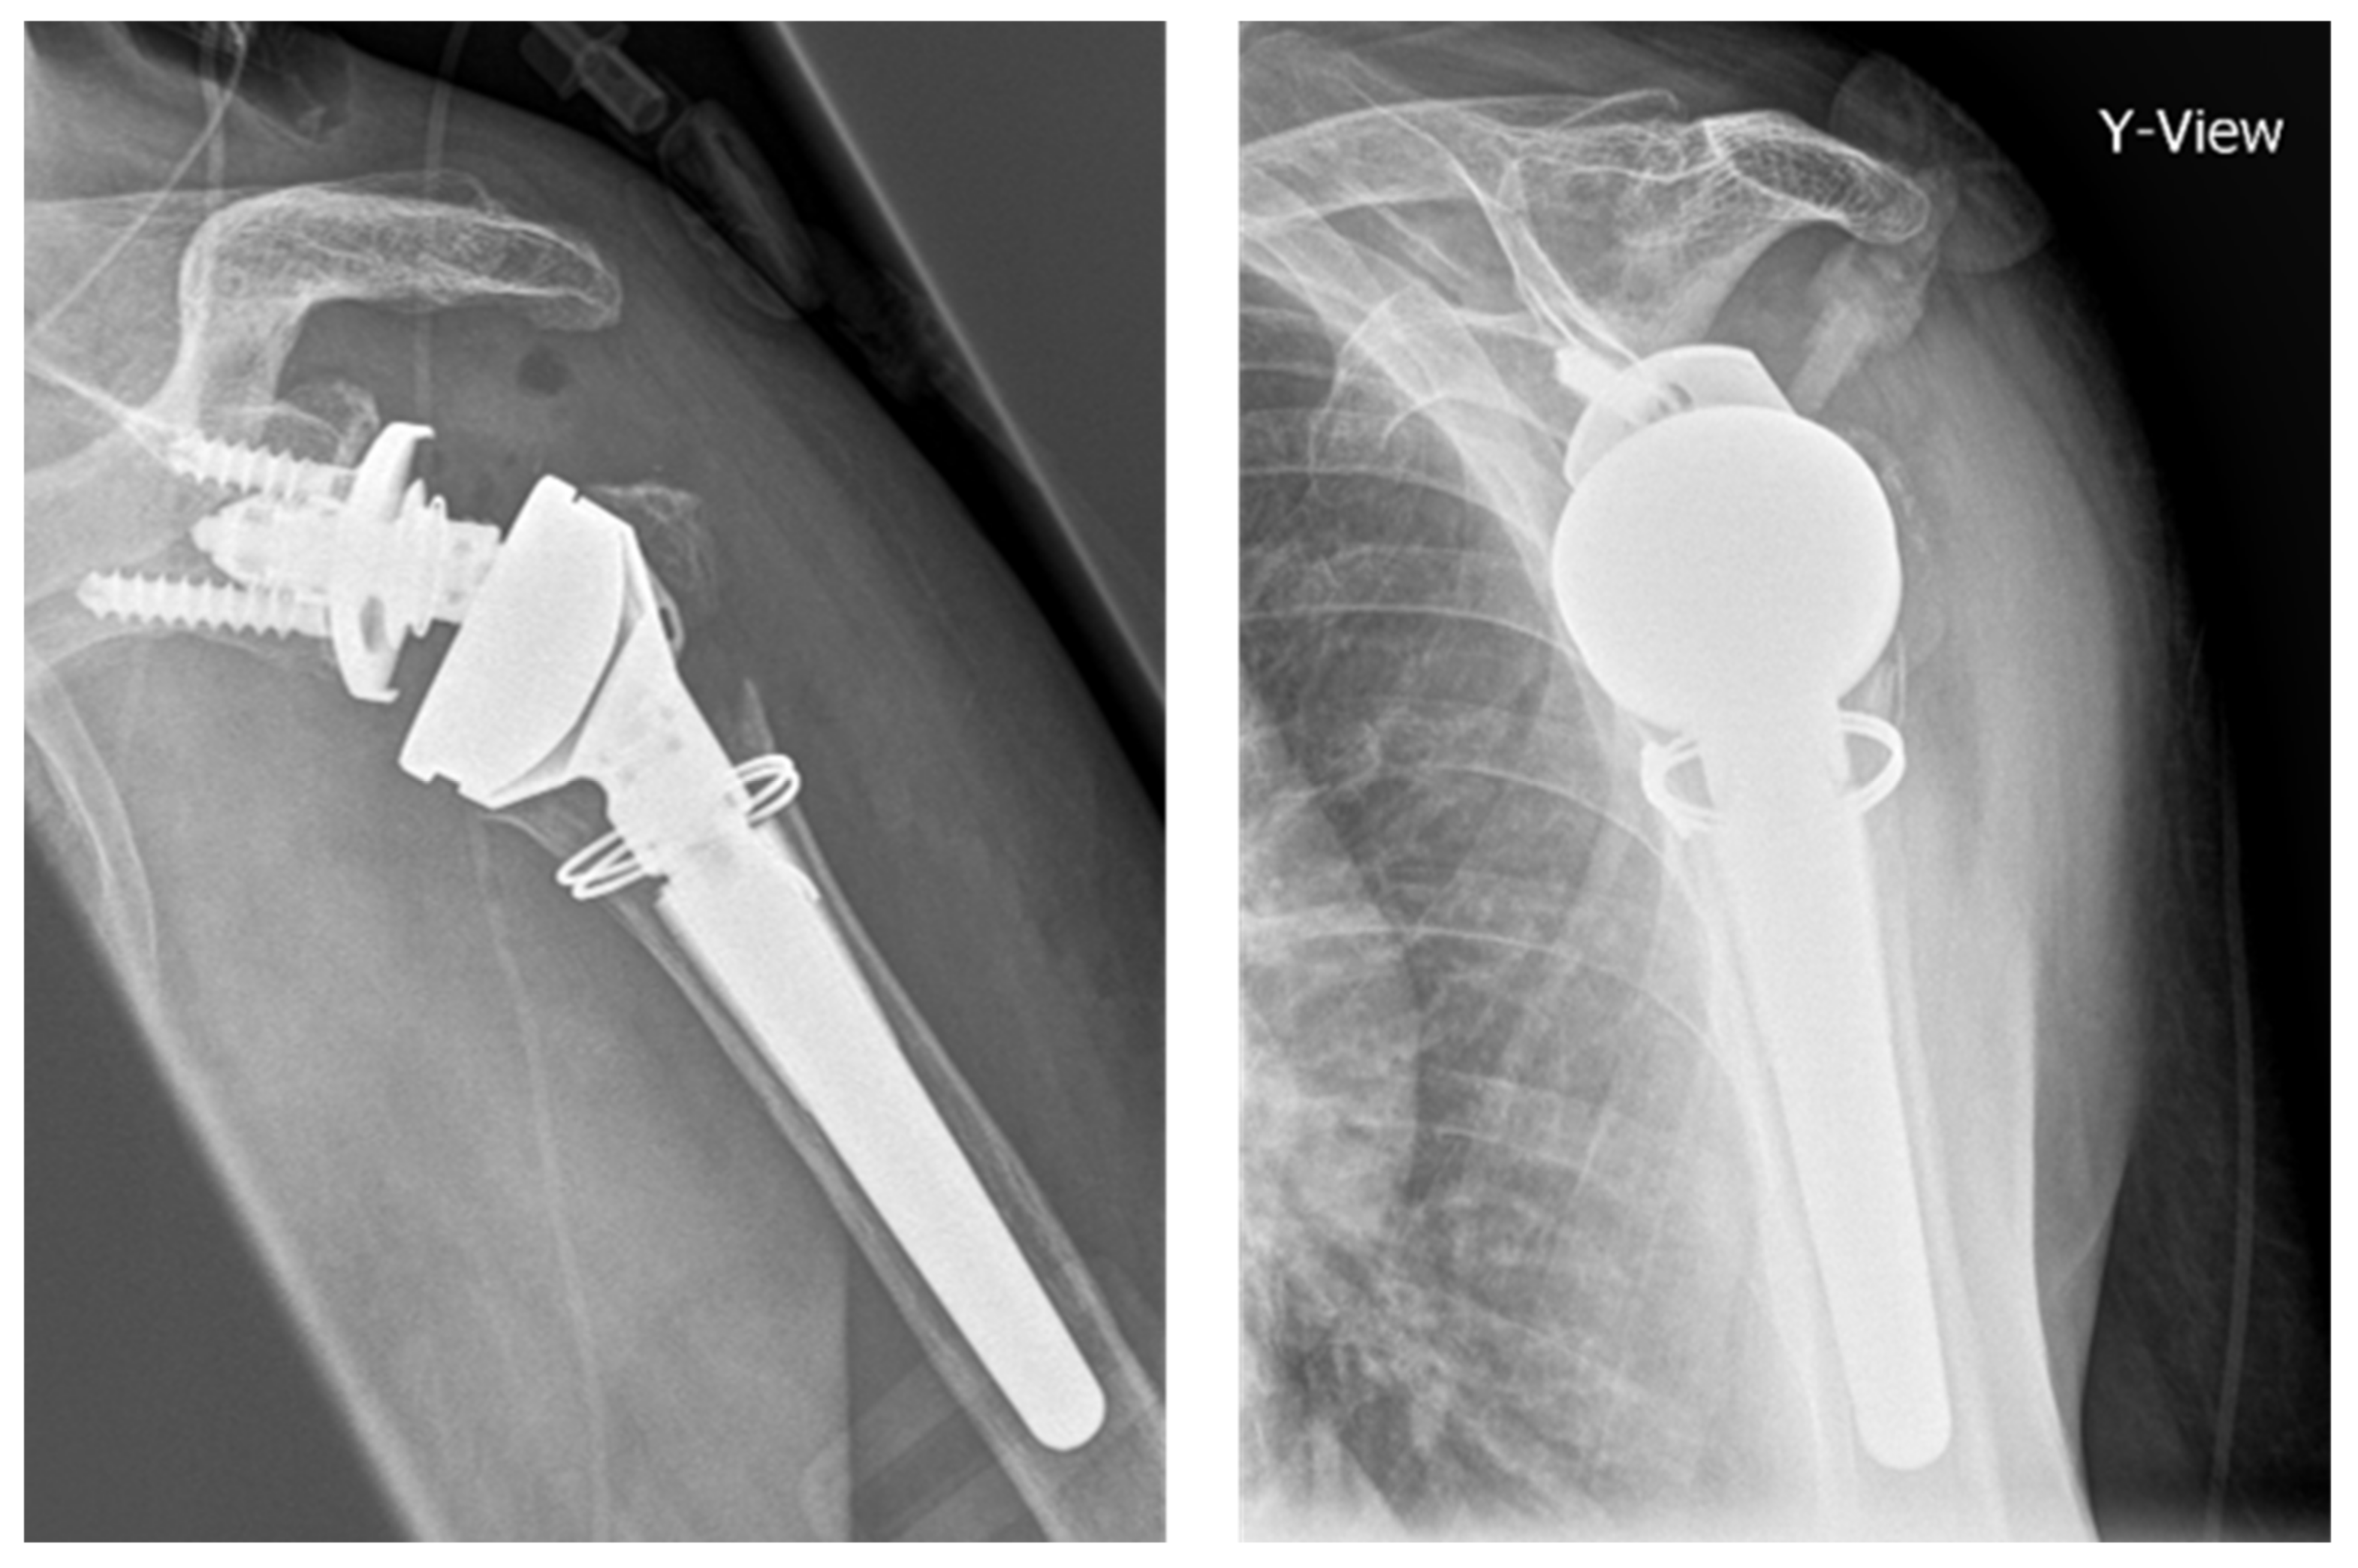

Shoulder Arthritis / Joint Replacement Reverse total shoulder

A Guide to Reverse Shoulder Replacement Surgery & Recovery Broken Screw In Shoulder Replacement Your surgeon will remove the. a shoulder replacement is a procedure that tries to eliminate the source of pain and dysfunction by replacing damaged parts of the shoulder joint with. usually, this will involve fixing the fracture fragments with plates, screws, or pins or peforming shoulder joint replacement. Carofino is an expert in shoulder replacement surgery, minimally invasive. Broken Screw In Shoulder Replacement.